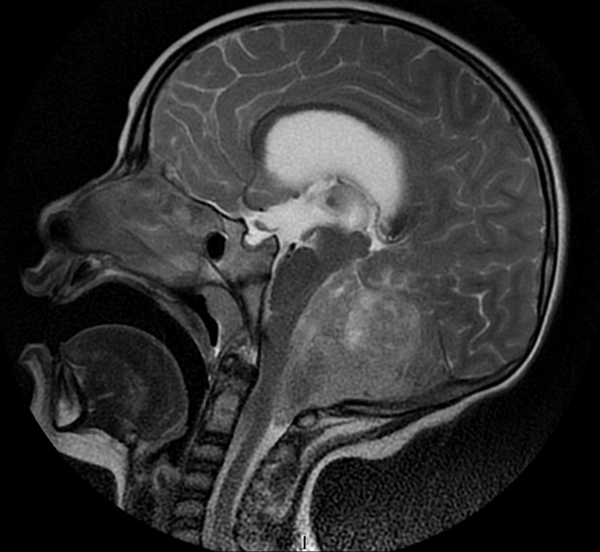

En resonancia magnética (RM) de cerebro se observa tumoración heterogénea sólida o sólido-quística con áreas de hemorragia, quistes y calcificaciones, que capta contraste en forma variable. (Fig. 1, 2, 3, 4). El patrón en espectroscopía se caracteriza por presentar pico de Colina (Cho) y descenso de N-Acetilaspartato (NAA).

Fig 4: RM corte sagital, secuencia T2. Se observa neoformación, solido-quística, iso-hiperintensa heterogénea de bordes irregulares en la topografía del VI ventrículo que ocupa la totalidad del mismo. Se proyecta caudalmente a través del foramen magno. Se evidencia colapso del VI ventrículo, desplazamiento del tronco cerebral hacia anterior y abombamiento del cuerpo calloso debido a la hidrocefalia obstructiva.